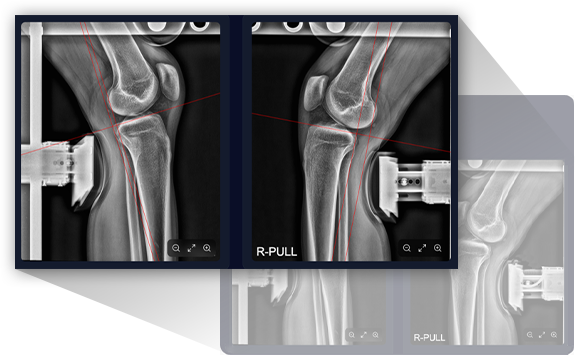

MADI-ACL is an AI-powered anterior cruciate ligament tear diagnostic solution.

It completely eliminates inter-observer variability and provides reliable, standardized diagnosis with 0.1mm precision.

We provide AI-powered image analysis for accurate and consistent ACL tear diagnosis,

delivering next-generation orthopedic diagnostic solutions with 0.1mm precision.